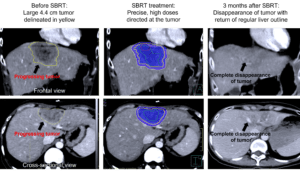

Aniela was 41 years old when she was diagnosed with Stage 4 breast cancer which had spread to the liver and bone in June 2021. Over the next one and a half years, she went through multiple lines of chemotherapy in her battle against the disease. On Aniela’s re-assessment scan in December 2022, it was found that the latest targeted treatment had worked well in most parts of her body. Unfortunately, there was a solitary liver nodule that had been stubbornly growing over the last 9 months. In recent months, this tumor had more than tripled in size, jumping from 1.4 cm to 4.4 cm.

In mid-December 2022, after 1.5 weeks of painstaking SBRT treatment plan preparation by Dr David and his team of physicists, Aniela began her treatment. During the pre-treatment verification scans routinely performed before each session of SBRT, it was found that even during the 1.5 weeks between the SBRT planning scan and day 1 of treatment, the tumor had increased in size by almost 10%. Fortunately, due to the team’s detailed planning and comprehensive knowledge of SBRT concepts, the safety margins that were applied to the initial tumor were sufficient to cover the additional areas of growth, and treatment was able to proceed as planned without further delay.

3 months after SBRT, on 29th March 2023, Aniela had a follow up scan to assess her response to treatment. A CT scan of the chest and abdomen revealed that the 4.4cm liver nodule had completely disappeared, with only an area of scarring and mild swelling seen at the previous disease site. This reflected a complete response to the SBRT treatment! Elsewhere in the body, there was no evidence of active cancer, and the previously treated areas in the bone and other parts of the liver with chemotherapy remained in remission.